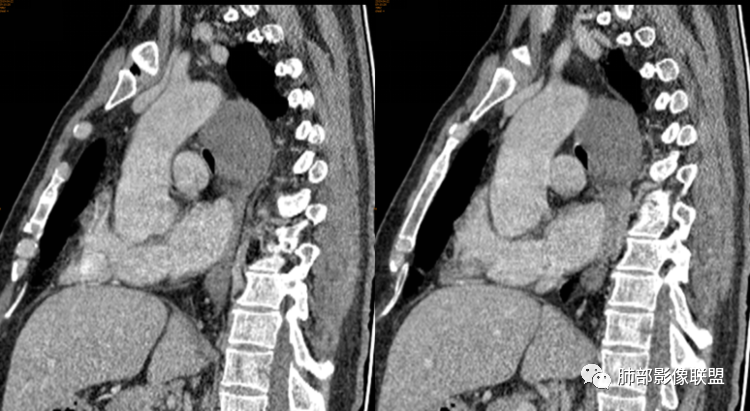

男性,43岁,体检发现后纵隔占位,边缘光整,CT示密度均匀,周围组织受压移位,无钙化囊变及脂肪组织,增强未见明显强化。MRI:T1示肿块信号较肌肉高,T2不均匀高信号。考虑为良性病变,第一是神经节细胞瘤,其次是支气管源性囊肿。

中年男性,无症状,后纵隔肿块,长径大矢状位于横径,质地偏软,塑形,等t1稍长t2,比较均质,增强轻微强化,与脊柱,主动脉,食管脂肪间隙存在,部分层面与脊柱相贴,骨质无改变,周围无肿大淋巴结,考虑神经源性肿瘤,节细胞神经瘤可能大,鉴别心包斜窦,淋巴瘤,淋巴管囊肿。

气管、左主支气管后方,食道左侧囊性占位,壁薄且均匀、光滑。气管及左主支气管受压凹陷、变形。

食道也受压变形、移位。